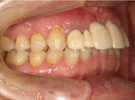

50代女性

![]() |

治療前 |

||

治療中。仮歯。 左上の奥にインプラント埋入。 噛みあわせ治療を行いました |

治療後 全体の歯で食事がおいしくできるようになったと喜んでおられました。 |